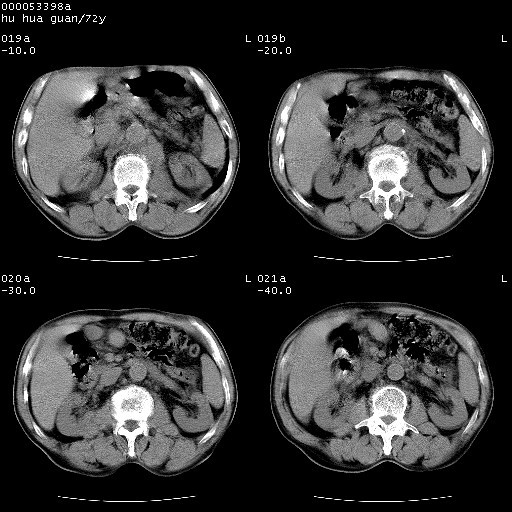

可以明确的说。肯定不是主动脉夹层破裂出血!考虑为淋巴瘤或间叶组织来源的恶性肿瘤可能性大。右肺小结节建议薄层观察,如能发现恶性征象,那椎前改变就考虑为转移所致。至于双侧少量胸水乃静脉血回流受阻所致。

后纵隔占位,降主动脉前移位;双侧胸腔积液;应排外食管病变侵犯血管可能;

建议排除结核引起的冷脓肿。